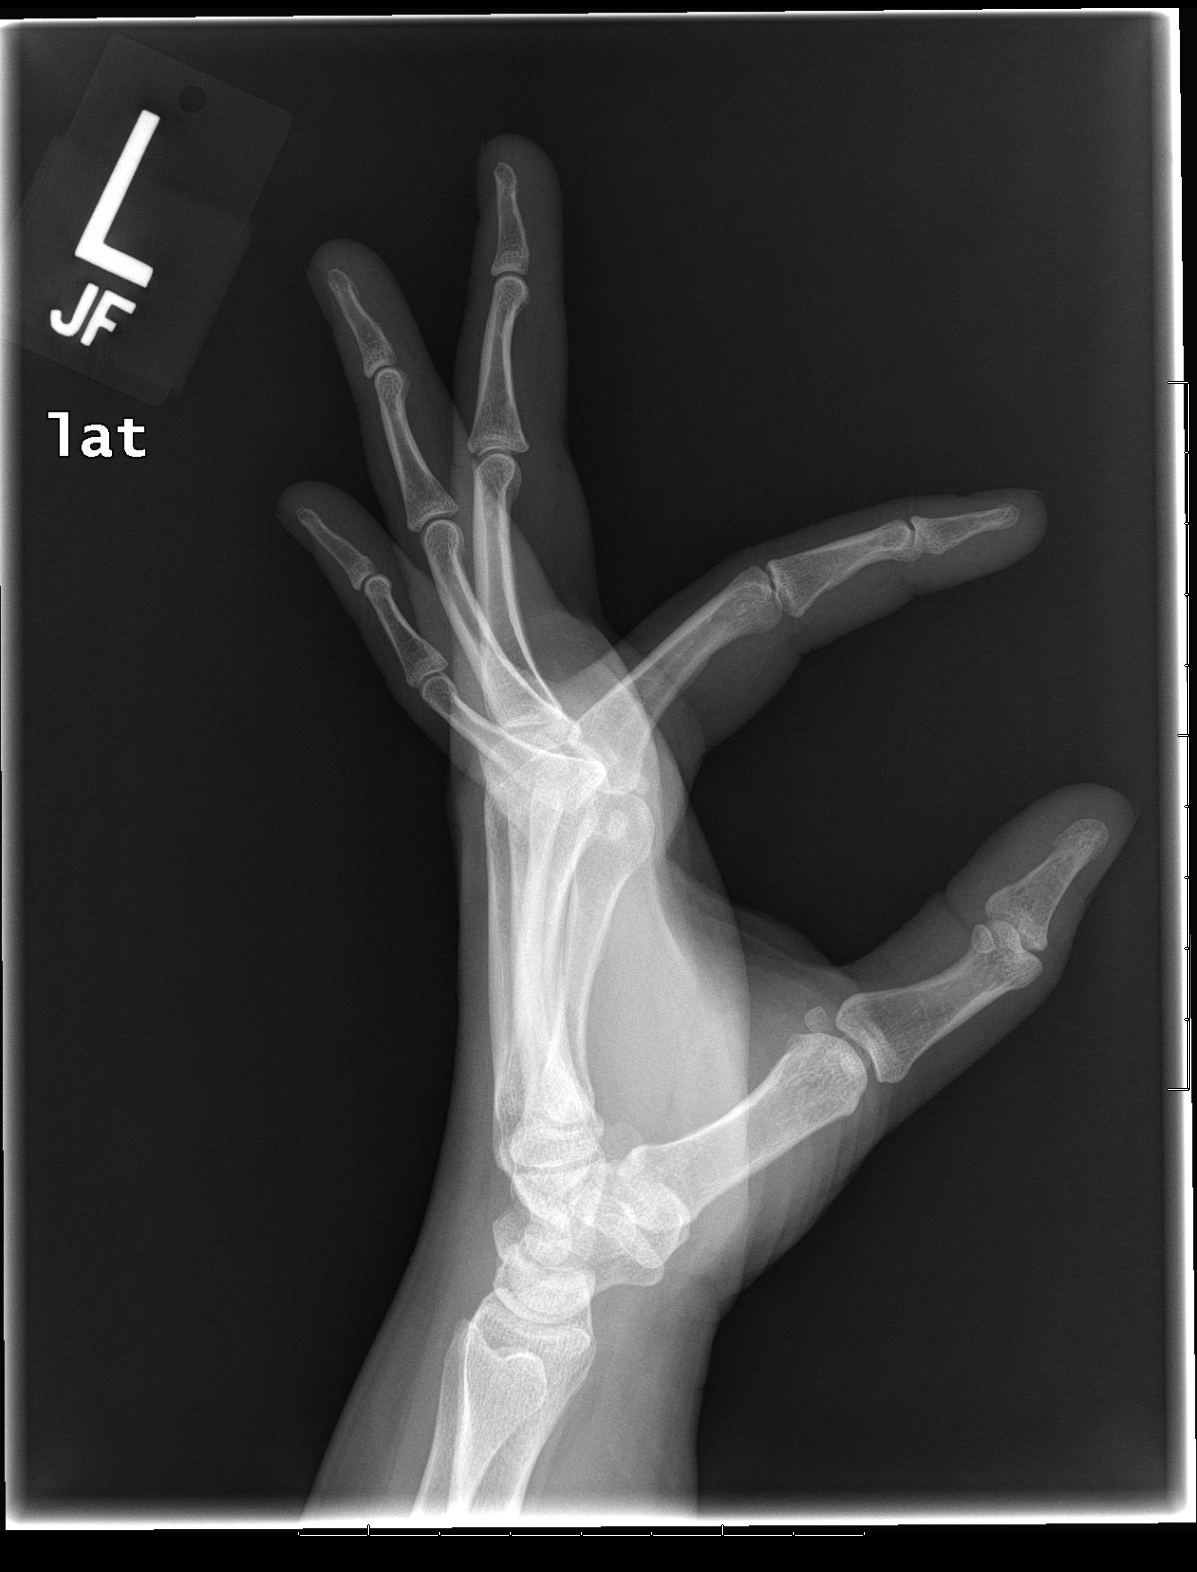

Lateral Hand X Ray Anatomy Left Hand X Ray Labeled The hand series consists of posteroanterior, oblique, and lateral projections. Oblique radiograph of the hand with labels. Although additional radiographs can be taken for. Frontal radiograph of the hand with labels. The hand comprises the metacarpal and phalangeal bones. There are 5 metacarpals in the hand. Head of the middle phalanx of index finger. Left Hand X Ray Labeled.

From www.researchgate.net